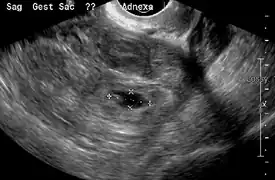

Transvaginal ultrasonography

An ultrasound showing a gestational sac with fetal heart in the fallopian tube has a very high specificity of ectopic pregnancy. It involves a long, thin transducer, covered with the conducting gel and a plastic/latex sheath and inserted into the vagina.[33] Transvaginal ultrasonography has a sensitivity of at least 90% for ectopic pregnancy.[5] The diagnostic ultrasonographic finding in ectopic pregnancy is an adnexal mass that moves separately from the ovary. In around 60% of cases, it is an inhomogeneous or a noncystic adnexal mass sometimes known as the "blob sign". It is generally spherical, but a more tubular appearance may be seen in case of hematosalpinx. This sign has been estimated to have a sensitivity of 84% and specificity of 99% in diagnosing ectopic pregnancy.[5] In the study estimating these values, the blob sign had a positive predictive value of 96% and a negative predictive value of 95%.[5] The visualization of an empty extrauterine gestational sac is sometimes known as the "bagel sign", and is present in around 20% of cases.[5] In another 20% of cases, there is visualization of a gestational sac containing a yolk sac or an embryo.[5] Ectopic pregnancies where there is visualization of cardiac activity are sometimes termed "viable ectopic".[5]

Transvaginal ultrasonography of an ectopic pregnancy, showing the field of view in the following image

A "blob sign", which consists of the ectopic pregnancy. The ovary is distinguished from it by having follicles, whereof one is visible in the field. This patient had an intrauterine device (IUD) with progestogen, whose cross-section is visible in the field, leaving an ultrasound shadow distally to it.- Ultrasound image showing an ectopic pregnancy where a gestational sac and fetus has been formed